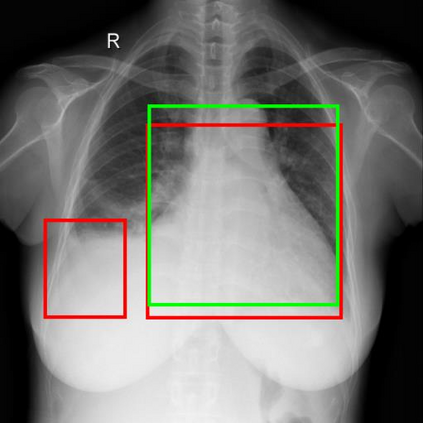

Chest X-ray (CXR) is the most typical diagnostic X-ray examination for screening various thoracic diseases. Automatically localizing lesions from CXR is promising for alleviating radiologists' reading burden. However, CXR datasets are often with massive image-level annotations and scarce lesion-level annotations, and more often, without annotations. Thus far, unifying different supervision granularities to develop thoracic disease detection algorithms has not been comprehensively addressed. In this paper, we present OXnet, the first deep omni-supervised thoracic disease detection network to our best knowledge that uses as much available supervision as possible for CXR diagnosis. We first introduce supervised learning via a one-stage detection model. Then, we inject a global classification head to the detection model and propose dual attention alignment to guide the global gradient to the local detection branch, which enables learning lesion detection from image-level annotations. We also impose intra-class compactness and inter-class separability with global prototype alignment to further enhance the global information learning. Moreover, we leverage a soft focal loss to distill the soft pseudo-labels of unlabeled data generated by a teacher model. Extensive experiments on a large-scale chest X-ray dataset show the proposed OXnet outperforms competitive methods with significant margins. Further, we investigate omni-supervision under various annotation granularities and corroborate OXnet is a promising choice to mitigate the plight of annotation shortage for medical image diagnosis.